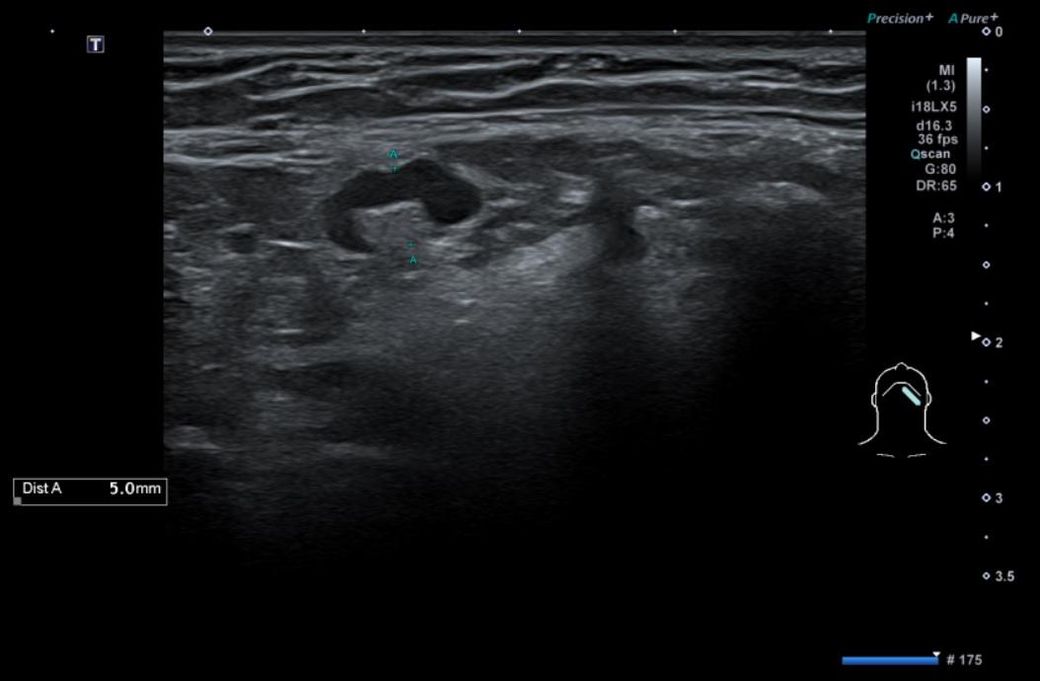

• 2번 째 사진